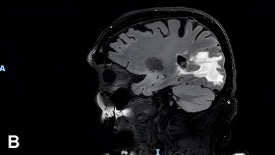

Following the initial brain MRI, a lumbar puncture (LP) performed during hospitalization revealed atypical lymphocytes but no immunophenotypic evidence of lymphoma. A subsequent LP, performed 2 days later, showed persistent pleocytosis without malignant cells. Six days after his initial brain MRI, a follow-up MRI demonstrated extension of the right occipital lesion with leptomeningeal enhancement along ventricular surfaces, brainstem, and cranial nerves (Figure 2A-B), raising continued concern for lymphoma or metastatic disease.

Figure 2A-B. MRI of the brain shows a right occipital lobe lesion extending to the lateral ventricle with abnormal contrast enhancement along ventricular, ependymal, and leptomeningeal surfaces. (A) Axial contrast-enhanced T1-weighted MRI demonstrating an irregular enhancing lesion that is centered in the right occipital lobe, extending toward the occipital horn of the right lateral ventricle. (B) Sagittal T2-weighted FLAIR MRI demonstrating extensive hyperintense signal within the right occipital and posterior parietal white matter that is consistent with vasogenic edema surrounding the lesion with mild local mass effect.